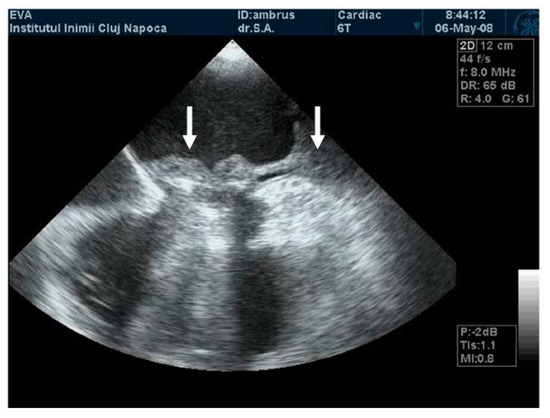

A pannus, in contrast to a thrombus, is a fixed mass with high echogenicity, comparable to that of the prosthetic ring (Figure 3). With the hyperplasia of connective tissue, it progresses from the ring to the prosthesis’ centre. It may also extend to the level of the hinges connecting the discs and the ring. Multidetector computer tomography (MDCT) is the method of choice to distinguish between thrombus and pannus [21,22]. For example, the degree of attenuation for the pannus has been consistently found to begreater than 150–200 Hounsfield Units (HU), while blood or even chronical thrombi have lower HU values [21].

Figure 3.

TEE. Obstructive pannus with high echo density on mechanical mitral valve prosthesis.